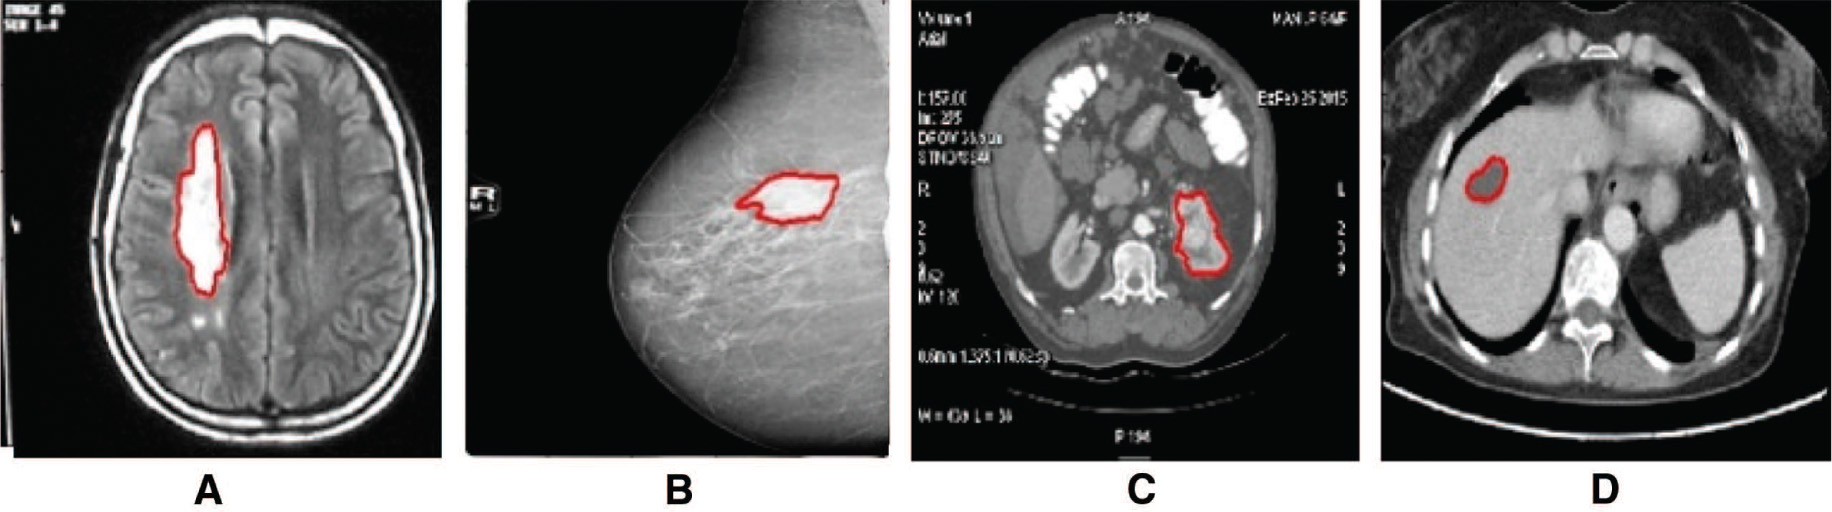

The results of region growing algorithm with manual seed point selection are depicted in Figure 3, and (x, y) represents seed point for the region growing technique. The threshold value of T = 0.2 is chosen for all the inputs, and the seed point coordinates will be a changing parameter, and it depends on the region of interest. The region growing process terminates when the intensity difference between the region mean and new pixel becomes greater than the threshold. Out of the conventional edge detectors, Canny algorithm generates efficient results. The Canny edge detection algorithm results are depicted in Figure 4. The Gauss gradient edge detector results are depicted here, and the parameter sigma plays a crucial role. For all the input images, sigma = 1.5 was chosen [43]. Boundary extraction is better in Gauss gradient edge detector technique. The gradient-based watershed algorithm results are depicted in Figure 5. Here, prior to segmentation, pre-processing was done by the median filter of kernel size 3 × 3.

Region Growing Algorithm Segmentation Result.

(A) (x, y) = (195, 145), (B) (x, y) = (175, 122), (C) (x, y) = (163, 103), (D) (x, y) = (80, 93).

Deformable Model for Tumor Boundary Extraction in Medical Images; Lankton Active Contour Segmentation Results.